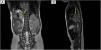

Se realiza ecografía posnatal en la cual se objetiva la resolución de la ectasia piélica izquierda, pero se informa de ausencia renal derecha. La ausencia de hipertrofia renal izquierda compensadora, descrita como tamaño renal superior al percentil 951 (en este caso la longitud era de 5cm: percentil 61,7) y los controles prenatales en los que se visualizaban ambos riñones, sugieren una posible ectopia renal2, por lo que se realiza gammagrafía con ácido dimercaptosuccínico (DMSA) marcado con Tc99m. Dicho estudio confirmó la sospecha clínica objetivándose la presencia del riñón izquierdo ortotópico y del riñón derecho en tórax (índice de captación renal: derecho 51%, izquierdo 49%) (fig. 1). Se amplía el estudio mediante ecografía torácica, resonancia magnética (fig. 2) y angio-TAC que confirman la presencia de hernia diafragmática que contiene: riñón derecho, asas de intestino delgado, ángulo hepático del colon sin anomalías vasculares.

Gammagrafía Tc99m DMSA. La captación a nivel renal izquierdo es normal en una localización ortotópica con distribución uniforme de la radioactividad. A nivel torácico derecho se detecta captación compatible con ectopia renal derecha. Índice relativo de captación renal: derecho 51%, izquierdo: 49%.